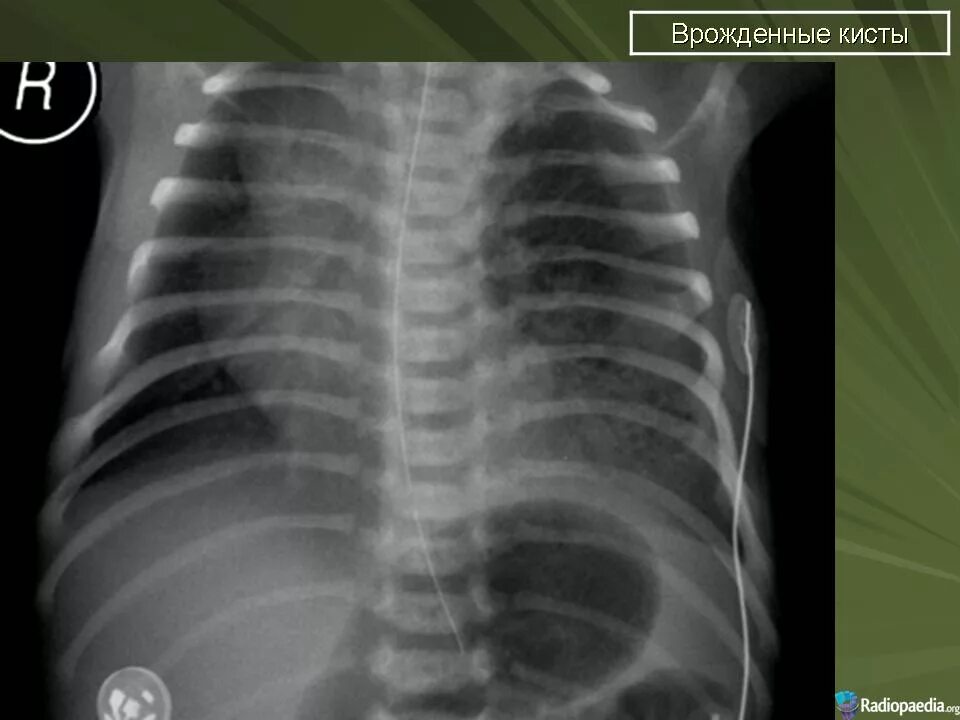

Гипоплазия 12 пары ребер